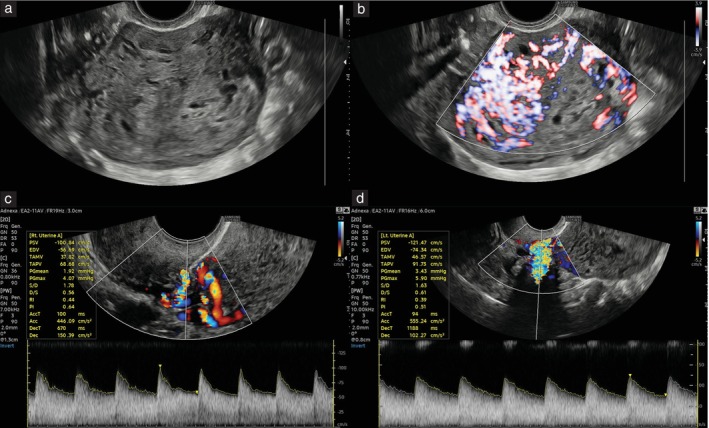

Methods: This was a single-center prospective cohort study involving ultrasound assessment of all GTN cases referred to and treated at the trophoblast unit of San Raffaele Hospital, Milan, Italy, between 2011 and 2023. TVS assessment included: grayscale analysis for the detection of myometrial or endometrial abnormalities, color and power Doppler assessment of lesions with scoring of vascularization, and spectral pulsed-wave Doppler for measurement of mean UtA-PI from the left and right UtAs. Sonographic findings were compared between patients with PSTT and those with other forms of GTN (postmolar, invasive mole or choriocarcinoma), using non-parametric two-tailed statistical analysis.

Results: A total of 73 GTN cases were recruited, comprising nine (12.3%) with PSTT and 64 (87.7%) with other GTN. A significant difference was detected between other-GTN and PSTT cases when comparing rates of substantial endometrial vascularity on Doppler (50% vs 0%; P = 0.013) and mean UtA-PI measurements (median, 1.5 (interquartile range (IQR), 1.0-2.4) vs 2.2 (IQR, 1.5-2.7); P = 0.014; area under the receiver-operating-characteristics curve, 0.768 (95% CI, 0.610-0.888)).

Conclusions: This study describes UtA-PI as a novel and effective marker allowing for the ultrasound differentiation of PSTT from other forms of GTN. The significantly higher mean UtA-PI and lower endometrial vascularity observed in PSTT as compared with other GTN suggests a unique vascularization pattern, with a potential role in differential diagnosis and management. © 2025 The Author(s). Ultrasound in Obstetrics & Gynecology published by John Wiley & Sons Ltd on behalf of International Society of Ultrasound in Obstetrics and Gynecology.